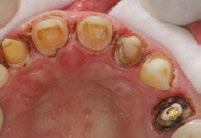

Figures 1 and 2: Example of staining from traditional MTA, non-vital bleaching after Figure 3: Pre-op Figures 4 and 5: Pulp cap Figures 6: Apexogenesis

With trauma protocols, we recall these patients quarterly for the first year prepared to intervene with traditional endodontic treatment anytime we see evidence of failure. We then see these patients annually for 5 years, or more often, until I am satisfied that the root growth is complete. Unfortunately, I was starting to see an ugly silver gray halo at the cervical margin as a result of the tooth erupting out of the alveolus as part of the normal growth of the child. All of a sudden, I was faced with another treatment challenge. Now I had to take out my minimalistic composite, remove MTA, and then remove tooth structure to facilitate non-vital bleaching. I remember being very frustrated that we were weakening tooth structure coronally after working so hard to grow the root. I also faced the possibility of damaging the pulp as we had to remove much of that 2 mm MTA cap.

Enter EndoSequence®. I remember my Brasseler rep coming to my office to fulfill my bur order. He asked me if I was familiar with this new bioceramic root repair material in a putty consistency. It has all the desirable qualities of my original MTA but also was the answer to my problems. Now there was a material which had amazing handling properties, did not require pre-mixing, and would bond to dentin because of its hydrophilic properties and very small particle size. A huge benefit was that it would not stain the dentin. At first being a purist, I was reluctant to change because I was so hooked on the benefits of my original MTA. I started using it first in my posterior apexogenesis cases where color was not a concern.